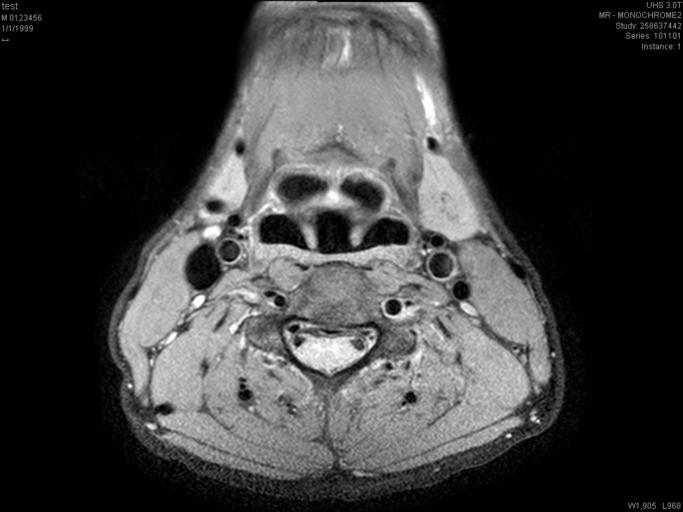

MAKE A MEME View Large Image Larynx PDW nima.jpg A not so good view of the larynx scanned by myself using an Achieva Philips 3T MRI system The image is a Proton Density weighted using the scanner's own PDW BB M2D CLEAR protocol A medium sense flex coil was attached to ...

Keywords: Larynx PDW nima.jpg A not so good view of the larynx scanned by myself using an Achieva Philips 3T MRI system The image is a Proton Density weighted using the scanner's own PDW BB M2D CLEAR protocol A medium sense flex coil was attached to the patient Own 2008 Zereshk Larynx Magnetic resonance imaging